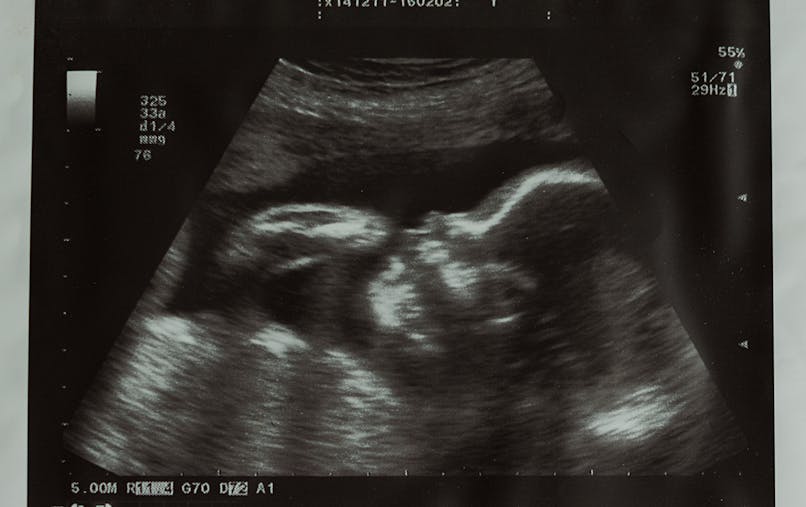

8 semaines de grossesse bébé a la taille d'une framboise La 8ème semaine de grossesse est marquée par le passage de l'embryon à une taille de 41 millimètres de la tête au coccyx, soit l'équivalent d'une framboise La tête de bébé est encore plus grande à côté du reste de son corps et on voit pointer son nezDéveloppement et comportement du bébé à 8 semaines de grossesse (10 SA) Votre bébé bouge mais vous ne ressentez pas encore ses mouvements Ses organes fondamentaux sont désormais présents, cependant tous ne sont pas encore fonctionnels Le cœur de votre bébé bat et vous pouvez désormais l'entendre grâce au DopplerTaille et poids du bébé à 8 semaines d'aménorrhée

Suivi de grossesse semaine par semaine Votre enfant À 8 semaines de grossesse votre embryon est devenu un fœtus, il mesure maintenant 3 cm et pèse en moyenne 2,5 à 3g !Votre bébé à 8 semaines de grossesse 10 SA6/03/21 · La 6e semaine de grossesse ou 8 SA, de notre côté Notre grossesse reste imperceptible aux yeux des autres Néanmoins, notre utérus a légèrement grossi et, du coup, on peut déjà se sentir un peu serrée dans ses vêtements, notamment au niveau de la taille Certaines hormones entraînent une augmentation de la production d'urine